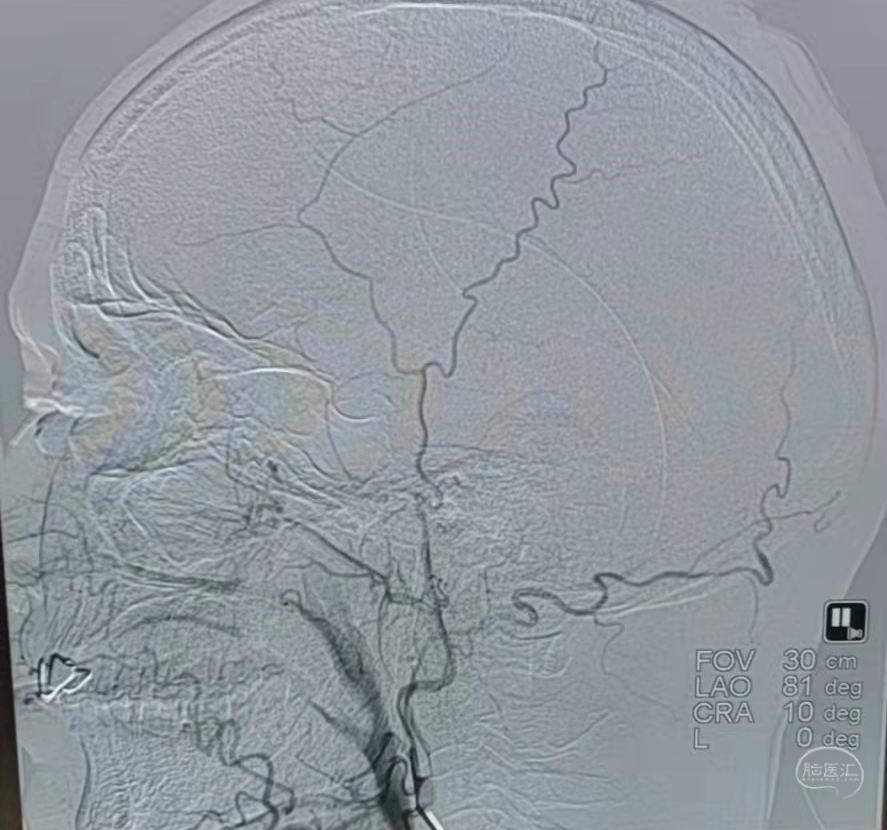

DSA:左侧颈内动脉闭塞。

颞浅动脉未向颅内代偿。

DSA:右侧大脑中动脉、大脑前动脉闭塞,烟雾样血管形成。

颞浅动脉未向颅内代偿。

DSA:左侧大脑中动脉、大脑前动脉闭塞,烟雾样血管形成。

颞浅动脉未向颅内代偿。

DSA:右侧大脑中动脉、大脑前动脉闭塞,烟雾样血管形成。

颞浅动脉未向颅内代偿。

DSA:左侧大脑中动脉、大脑前动脉闭塞,烟雾样血管形成。

颞浅动脉未向颅内代偿。